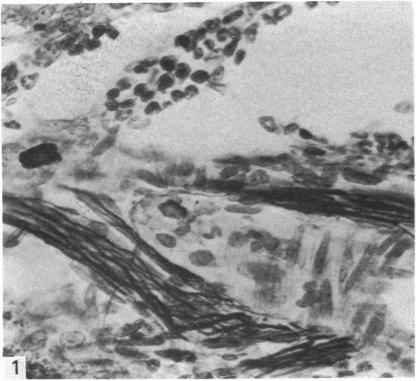

Distribution of nerves in long bones as shown by silver impregnation.

J Anat. 1982 Jun;134(Pt 4):719-28.